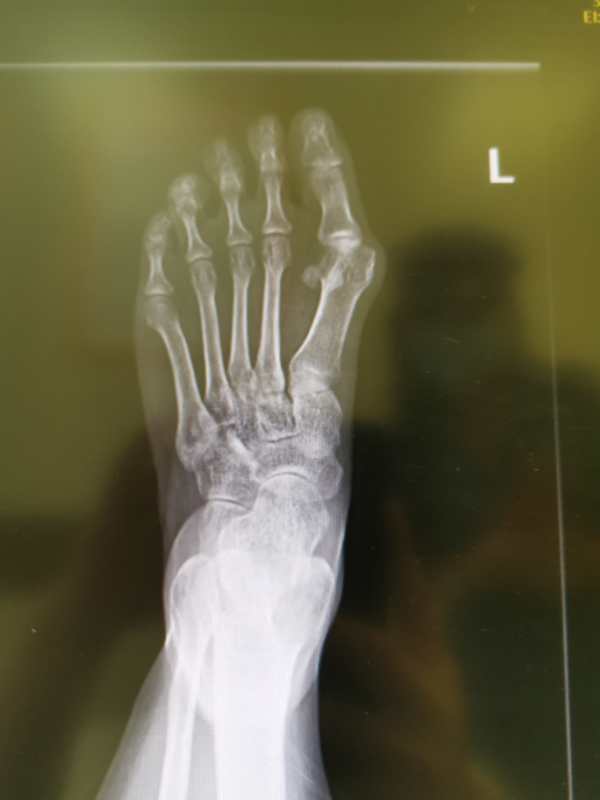

拇外翻x线